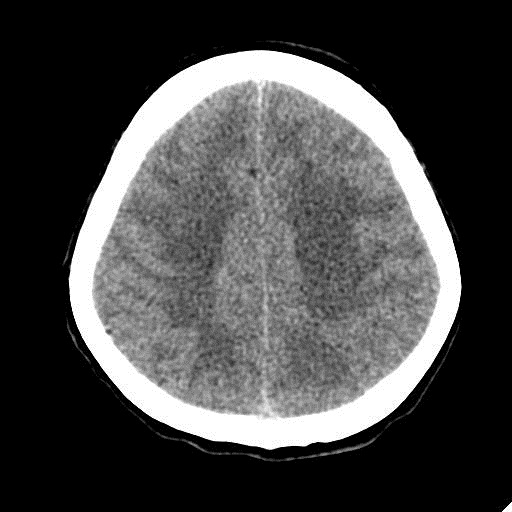

КТ головного мозга, кровоизлияние.

"Скорая" привезла женщину 75 лет, найденную на улице. На КТ направлена с д-зом: кома неясного происхождения. Вот такая картина на КТ.

PS. Не очень понял про ///отек мозга///, есть снижение плотности (отек и ишемия) белого вещества левого полушария и задних отделов правого.

Про отек: субарахноидальных щелей совсем нет, по белому веществу и в стволе снижение плотности, извилины утолщены, серое вещество на этом фоне выглядит более светлым, толстым, подушкообразным.

Причина таких кровоизлияний, как правило, гипертензия и атеросклероз.